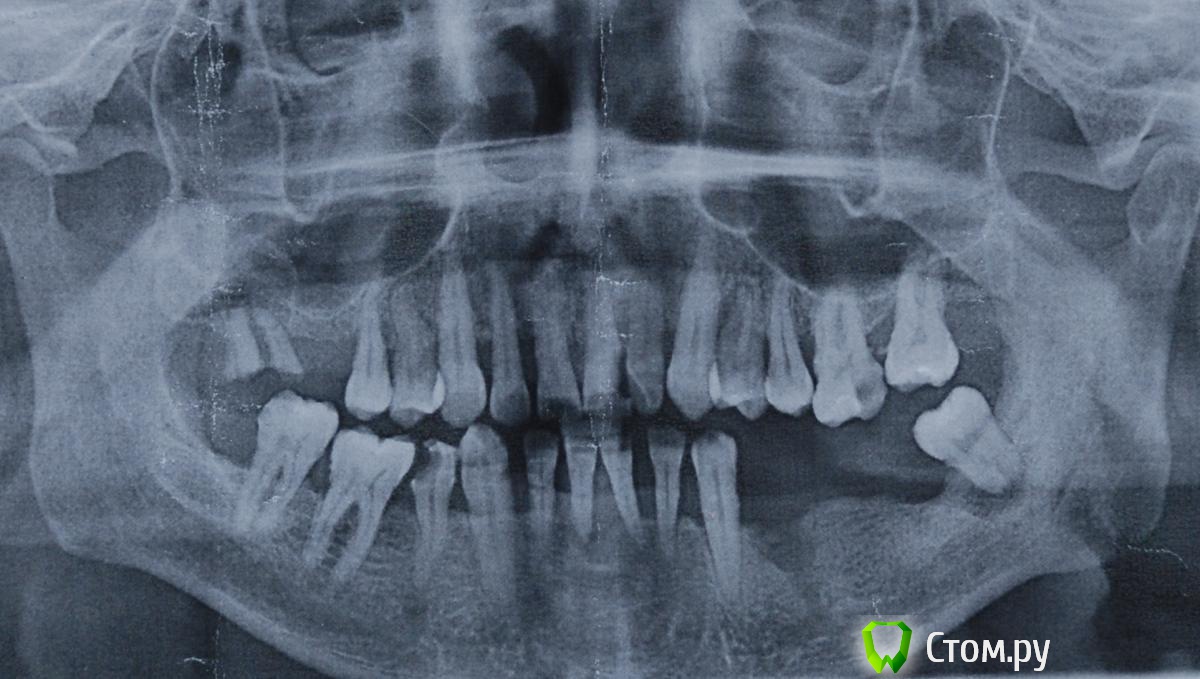

Alex02 Опубликовано 8 ноября, 2014 Поделиться Опубликовано 8 ноября, 2014 Доброго времени суток всем присутствующим. Позвольте представиться. Алексей, 46 лет, не пью(вааще ), не курю(3 месяца), в порочащих связях замечен не был . А теперь о грустном. Решил плотно заняться лечением зубиков. Причина банальна - после того, как бросил курить, появился неприятный запах изо рта, хотя гигиену соблюдаю. Начали шататься некоторые зубы. В общем, пичалька. Набросал для себя список неотложных мероприятий по приведению в порядок своей ротовой полости и понеслась...1. Сходил на приём к терапевту, где после тщательного осмотра выяснилсь, что необходимо удалить 34(уже удалён),37,17(готовы к удалению), 31,41 - шатаются и готовы к удалению.2. Сделал профчистку. Лечу и пломбирую всё, что ещё поддаётся лечению.3. Коплю деньги .Ну а теперь самое интересное. Собираюсь убрать 31,32,41,42 и одномоментно на место 32,42 поставить имплантаты с дальнейшей установкой моста. Вместо отсутствующих 34, 36 установка имплантатов с дальнейшей установкой моста. Хорошее правило - 1 имплантат=1 зуб не потяну по финансовым соображениям. Склоняюсь к установке Alpha Bio, как хорошего середнячка по соотношению цена-качество.Уважаемые врачи, покритикуйте пожалуйста вышеизложенное и поделитесь своим видением ситуации. Буду рад услышать ваше мнение. Ссылка на комментарий

faity Опубликовано 9 ноября, 2014 Поделиться Опубликовано 9 ноября, 2014 1.7, 1.4, 2.4, 2.5, 2.6, 2.7, 3.8, 3.2, 3.1, 4.1, 4.2, 4.7 под снос 3 моста на 3-х имлантахна счет остального по КТ Ссылка на комментарий

Alex02 Опубликовано 9 ноября, 2014 Автор Поделиться Опубликовано 9 ноября, 2014 Охтыжбожемой! Как страшно жить на белом свете... Неужели всё так запущено?На КТ записался на следующий понедельник, выложу сразу после получения на руки.В приоритете на данный момент стоит восстановление НЧ, особенно 3.1,3.2,4.1,4.2 и 3.4,3.5,3.6,3.7Какие у меня варианты по имплантации указанных позиций? Возможно ли установить имплантаты одномоментно вместо 3.2,4.2 и сделать мост между нижними клыками(безметалловая керамика)? Какое минимальное количество имплантатов необходимо для моста 3.4 - 3.7(металлокерамика)? 3.8 и 1.7 уберутся в ближайшее время. В верхней челюсти пока ещё зубики не шатаются и не беспокоят, займусь ими чуть позже. Ссылка на комментарий